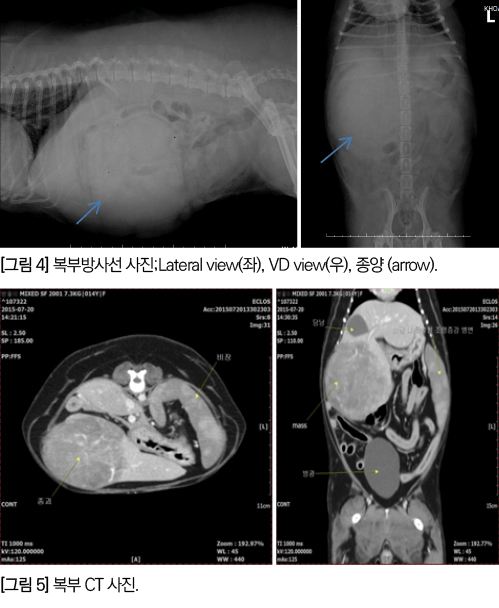

영상 검사상 10.5×8.4㎝ 크기의 soft tissue opacity를가진 mass가 오른쪽 upper abdomen에서 확인되었습니다[그림 4].

CT 영상에서 좌측외측엽에서 기원한 것으로 판단되는 약 10×8×10cm 정도의 큰 종괴가 우측 복배쪽으로 자라나 있으며, 종괴의 크기 및 조영양상 등을 고려 시 원발성 간종양으로 판단되었습니다[그림 5].